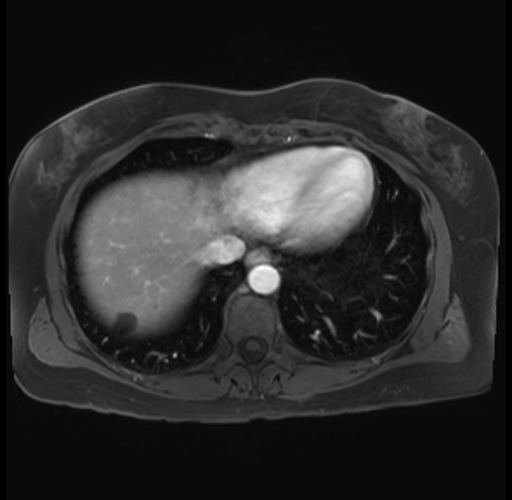

Imaging Analysis

Look through the patient's CT scan to identify any areas of concern for the necessary procedure.

Based on your CT findings, which issue(s) are present and would give reason for "planned slowing down moment(s)" in this case?